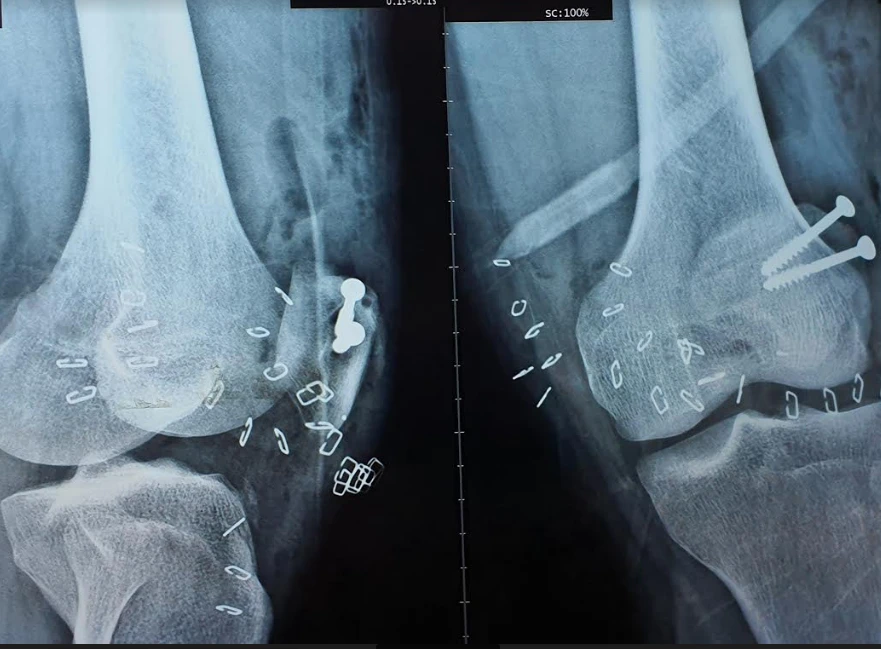

Chân phải ông H. bị gãy do chân vịt ca nô chém. Ảnh: BV CUNG CẤP

Tại đây, ông H. được chẩn đoán gãy hở xương cẳng chân phải giờ thứ 4, gãy hờ xương bánh chè chân trái và vết thương cổ tay phải. Các BS nhanh chóng cắt lọc thám sát khâu gân cơ, đặt khung cố định ngoài cẳng chân phải và kết hợp xương bánh chè trái. Hiện sức khỏe ông H. đã ổn định.